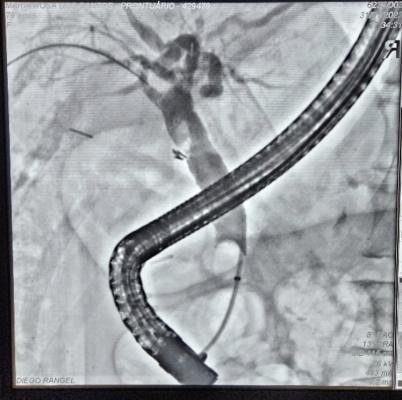

Paciente manteve assintomática e acompanhamento ambulatorial para programação de tratamento definitivo, que foi optado pela dilatação da via biliar (balão CRE 6-8mm) e inserção de prótese metálica auto-expansível totalmente recoberta (10 x 80mm) (Fig 5). O procedimento foi realizado 90 dias após a primeira CPRE sem intercorrências e optado pela retirada após 1 ano. A última CPRE foi realizada 12 meses após a inserção da prótese metálica no qual foi possível retirá-la, extrair o cálculo da via biliar proximal e obter uma colangiografia sem sinais obstrutivos ou extravazamentos ao final do procedimento (Fig 6).

Fig 6. Imagens colangiográficas da última CPRE: A. Imagem radiológica da prótese metálica inserida no procedimento anterior; B. Imagem colangiográfica de coledocolitiase em via biliar proximal; C. Colangiografia de oclusão final.